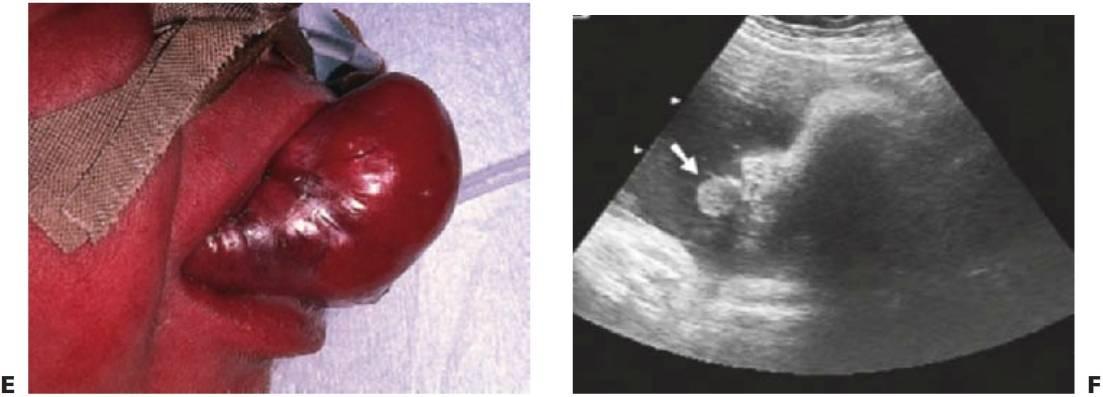

Síndrome de Stevens-Johnson

La enfermedad se presenta con fiebre aguda, exantema generalizado, lesiones que afectan a la cavidad oral y una conjuntivitis purulenta grave. Las lesiones cutáneas son más extensas que las del eritema multiforme. El síndrome de Stevens-Johnson se caracteriza por erupciones vesiculoampollosas en todo el cuerpo, sobre todo en el tronco, y afecta gravemente a múltiples membranas mucosas, incluyendo la vulva, el pene y la conjuntiva. El curso de esta enfermedad es más largo y puede dejar cicatrices. Algunos autores han empleado el término «eritema multiforme mayor» para el síndrome de Stevens-Johnson y han definido este cuadro como una forma grave del eritema multiforme, sin embargo otros lo discuten. Si bien los pacientes afectados por el síndrome de Stevens-Johnson están gravemente enfermos, con poca frecuencia se produce fallecimiento (fig. 8.7E, F).